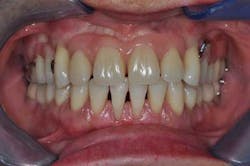

A 40-year-old woman, with no medical history except that she is a smoker (five cigarettes a day), is visiting us for an oral rehabilitation. Her chief complaints are teeth mobility and an esthetic concern since her maxillary front teeth are moving forward. The patient also suffers from dental anxiety.

Diagnosis

The patient’s main problem is adult aggressive periodontitis, aggravated by tobacco use. The consequent tooth losses have caused migrations of the remaining teeth under functional adaptation.

- Periodontal: Risk is high because of the advanced periodontitis. Prognosis is hopeless for teeth Nos. 5, 12, 15, and 18. It is poor for teeth Nos. 1, 2, 3, 6, 8, 9, 10, and 11 and considered fair for mandibular teeth Nos. 20 through 29.

- Dental: No carious or erosive lesions have been diagnosed. Only tooth No. 1 holds a small Class II amalgam on the mesial. Thus, the prognosis for all the remaining tooth structure is good.

- Functional: Clinical examination did not show any dysfunction of the musculo-articular structures. Prognosis of the oral function after prosthetic rehabilitation is good.

- Esthetics: The patient’s relatively young age and her esthetic concern are at the core of her desire to seek care. Her smile line is intermediate. Her anxiety makes the esthetic prognosis poor.